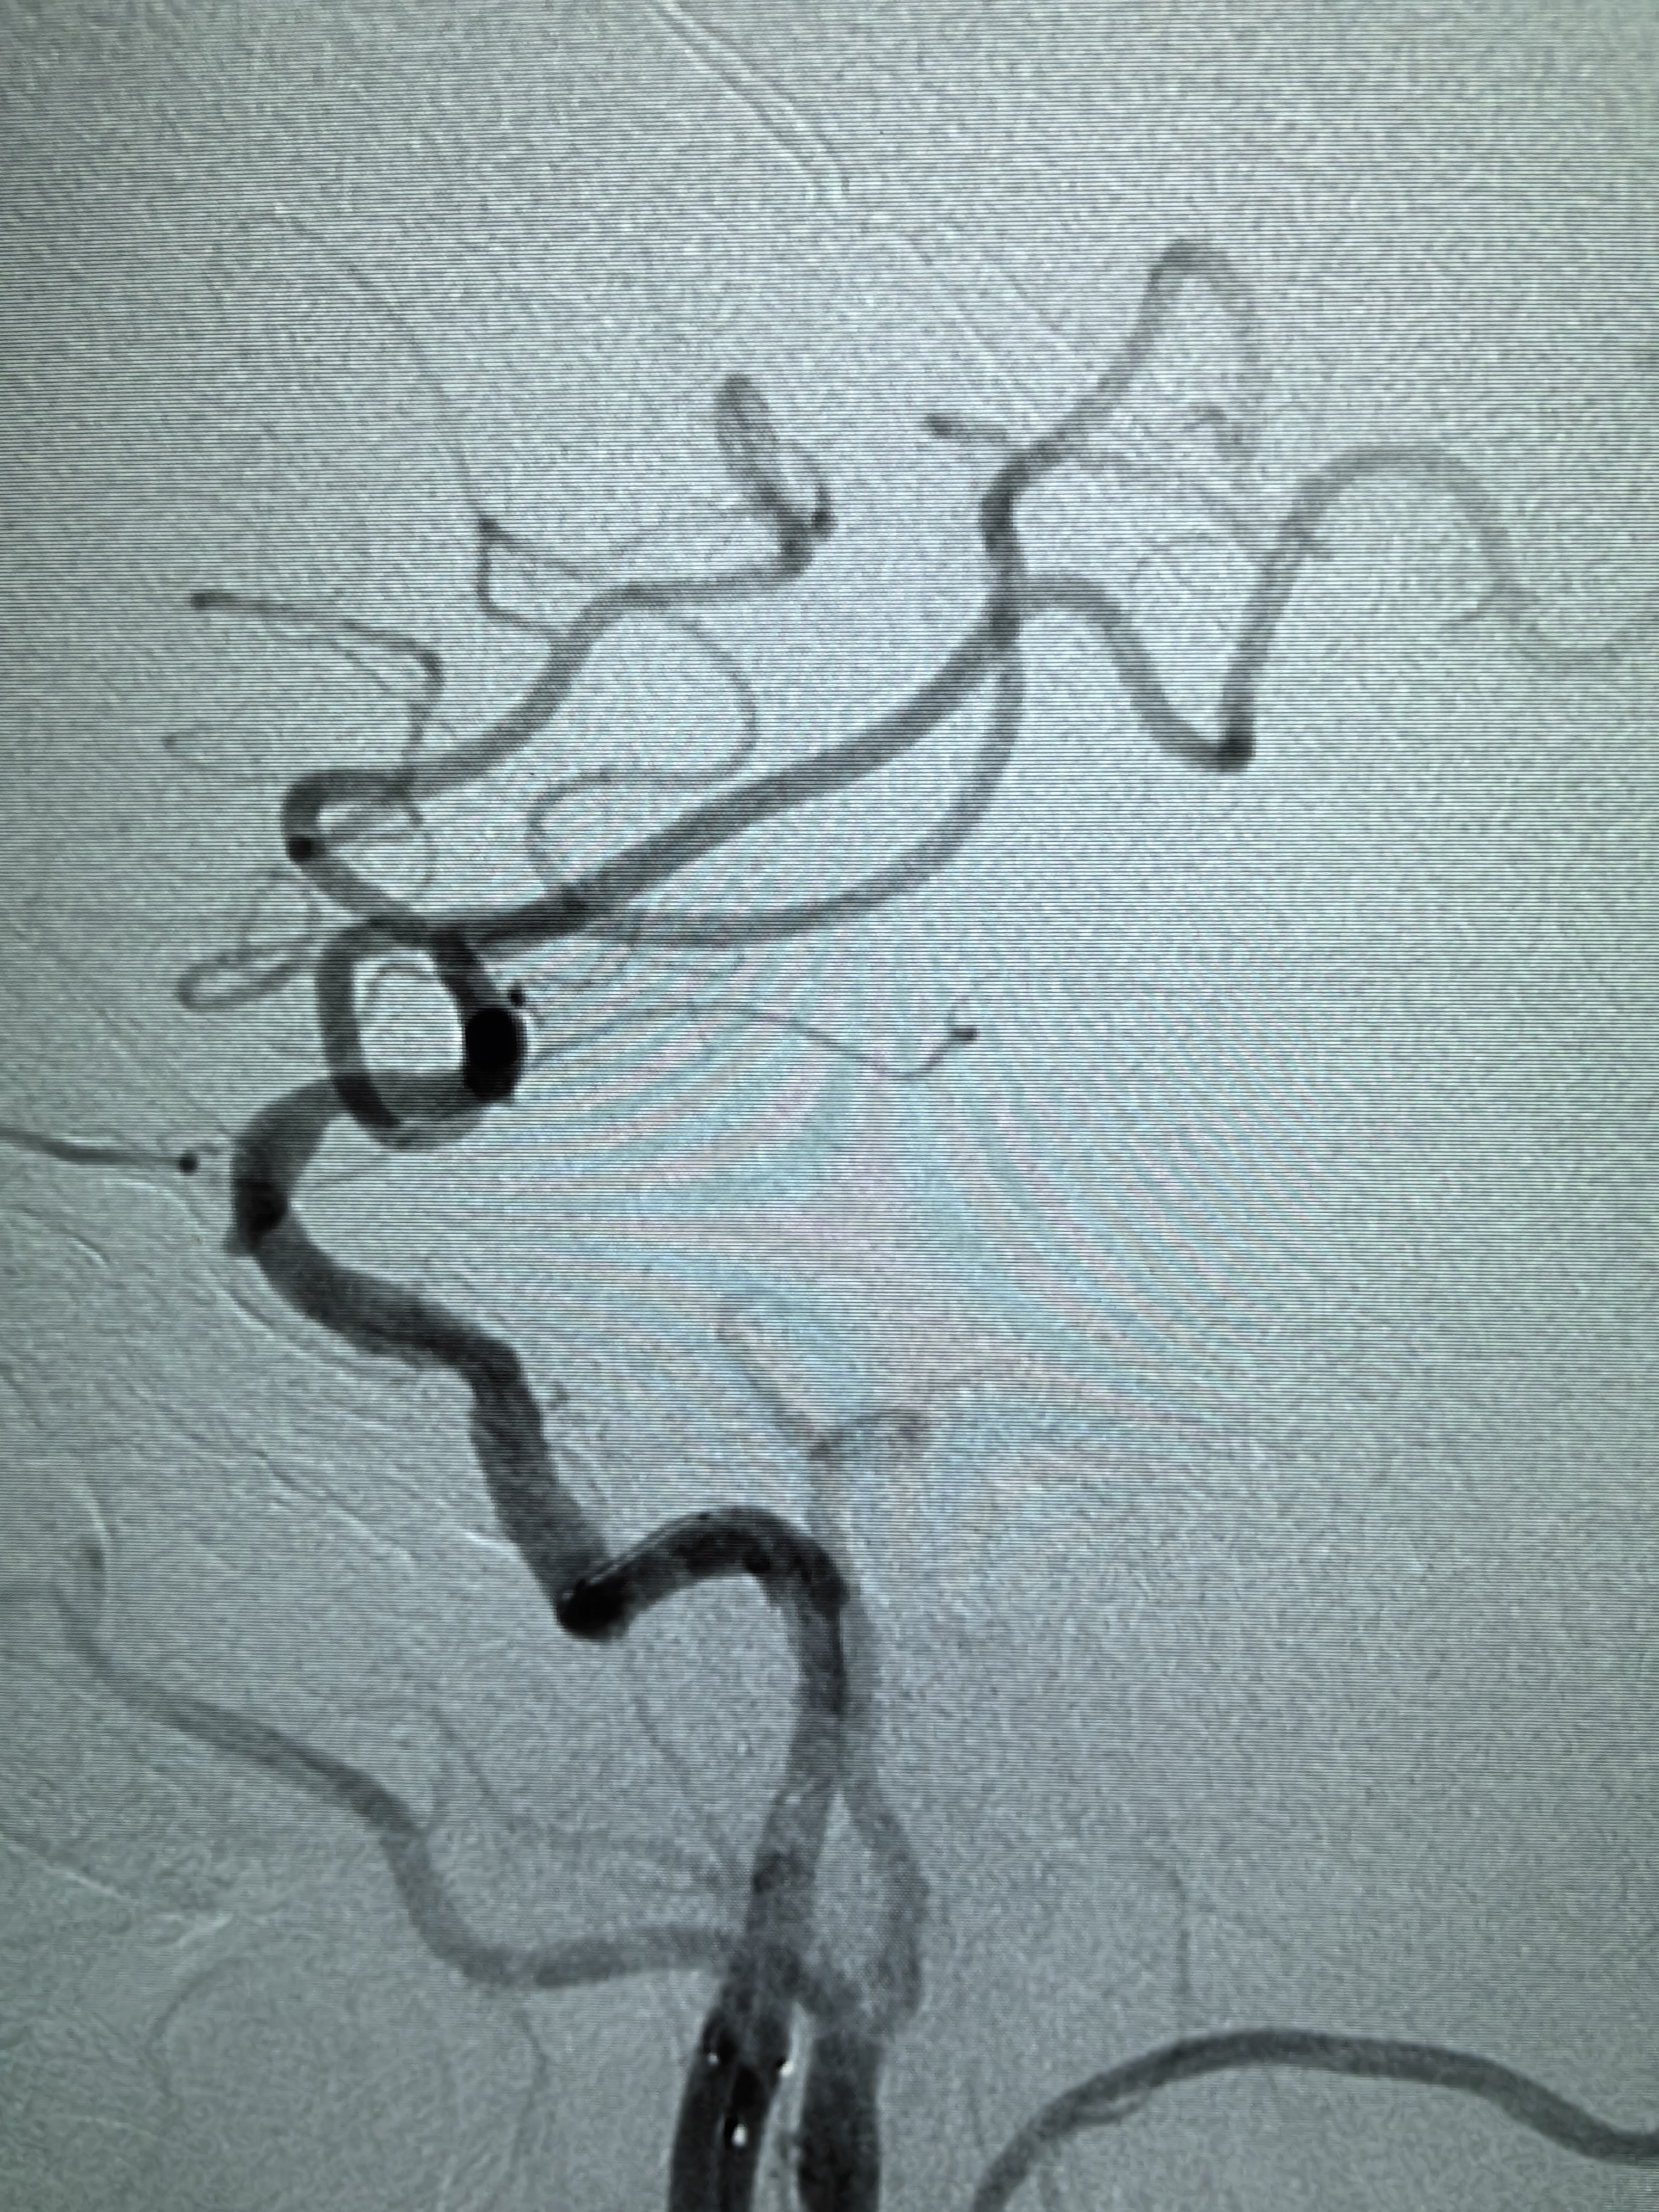

患者男性,70岁,体检发现双侧颈内动脉重度狭窄,1月前行右侧颈内动脉支架成形术,现为治疗左侧颈内动脉狭窄入院。既往高血压病史30年,口服硝苯地平控释片降压,血压控制130/80mmHg。

1、本例患者老年男性,双侧颈内动脉重度狭窄,治疗采取分期处理,间隔4周。

2、左侧颈内动脉从CTA看狭窄合并软斑,具备介入治疗指征。